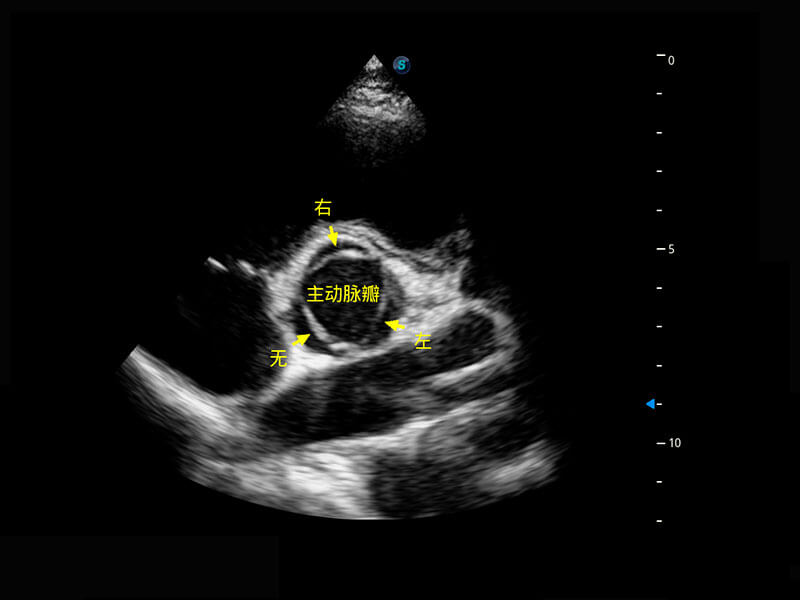

P60搭载一系列胎儿心脏成像技术,实现精细的胎儿心脏评估。

四腔切面

胎心容积成像